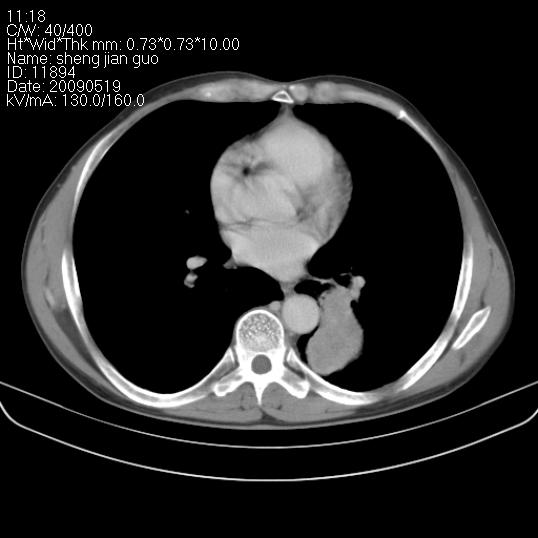

以下是引用zjzjr在2009-5-19 17:25:00的发言:[br]支持楼主考虑,另左肺下叶阻塞性炎症。

以下是引用zhao_bin2008在2009-5-19 17:48:00的发言:[br]支持左肺下叶周围型肺癌并阻塞性肺炎。

以下是引用zsl6918在2009-5-20 7:10:00的发言:[br]左侧中心型肺癌!